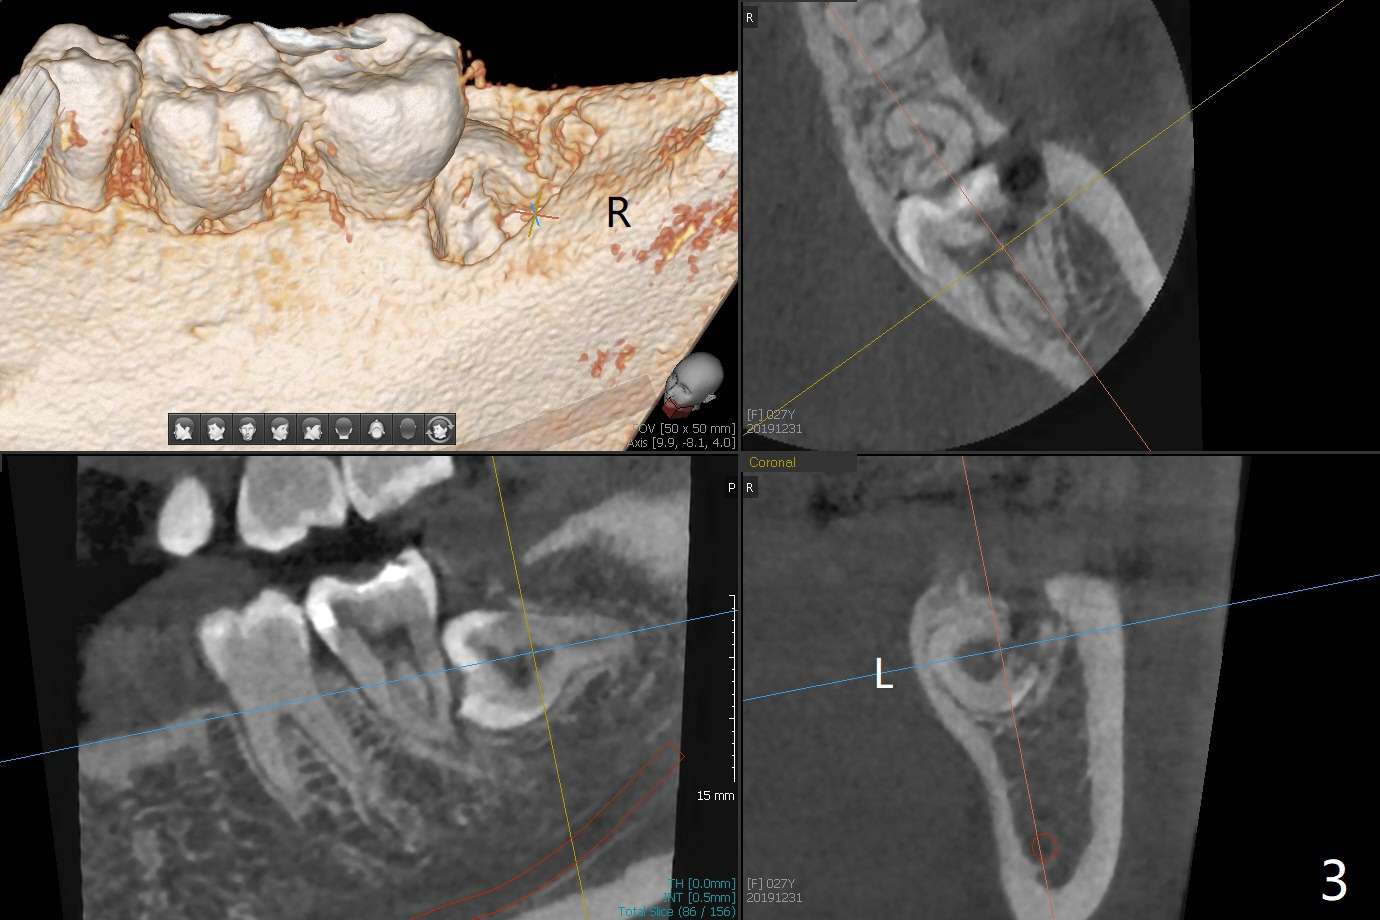

A 27-year-old woman (nervous) is going to return for #16 and 17 extraction (Fig.1). Offer sedative (Valium) if she cannot overcome fear. Take PAs for #17 and 32 to confirm Buccal Impaction, which dictates position of the accessory incision to reduce loss of bone graft in case of wound dehiscence. Place Collagen Plug (1/2 piece) in the apical portion of the sockets of the lower 3rd molars, while Augma and Osteogen Plug (1 piece) in the coronal half of #17 and 32, respectively. Place additional Collagen Plug for the remaining socket if needed before 4-0 PGA suturing as the 2nd step to decrease the chance of losing bone cement. Preop PA shows that the tooth #17 seems to be mesial (Fig.2 arrow). The accessory incision is placed mesiobuccal of the tooth #18 (Fig.4 red oblique line, Fig.6) so that it is not overlying the bony defect (Fig.4 arrowheads). Since the access to the impacted tooth is limited, small field of CT is taken (Fig.3,4), which shows the root is yet to be exposed (Fig.3 R). After tooth removal, Collagen plug is placed in the apex of the socket for hemostasis (Fig.5 C), while Bond Apatite coronal for bone regrowth (A). There is no dehiscence 11 days postop (Fig.7), although the patient complains of pain in the jaw and the temporomandibular region. The anterior portion of the external oblique ridge forms 1 year 7 months postop (Fig.8).